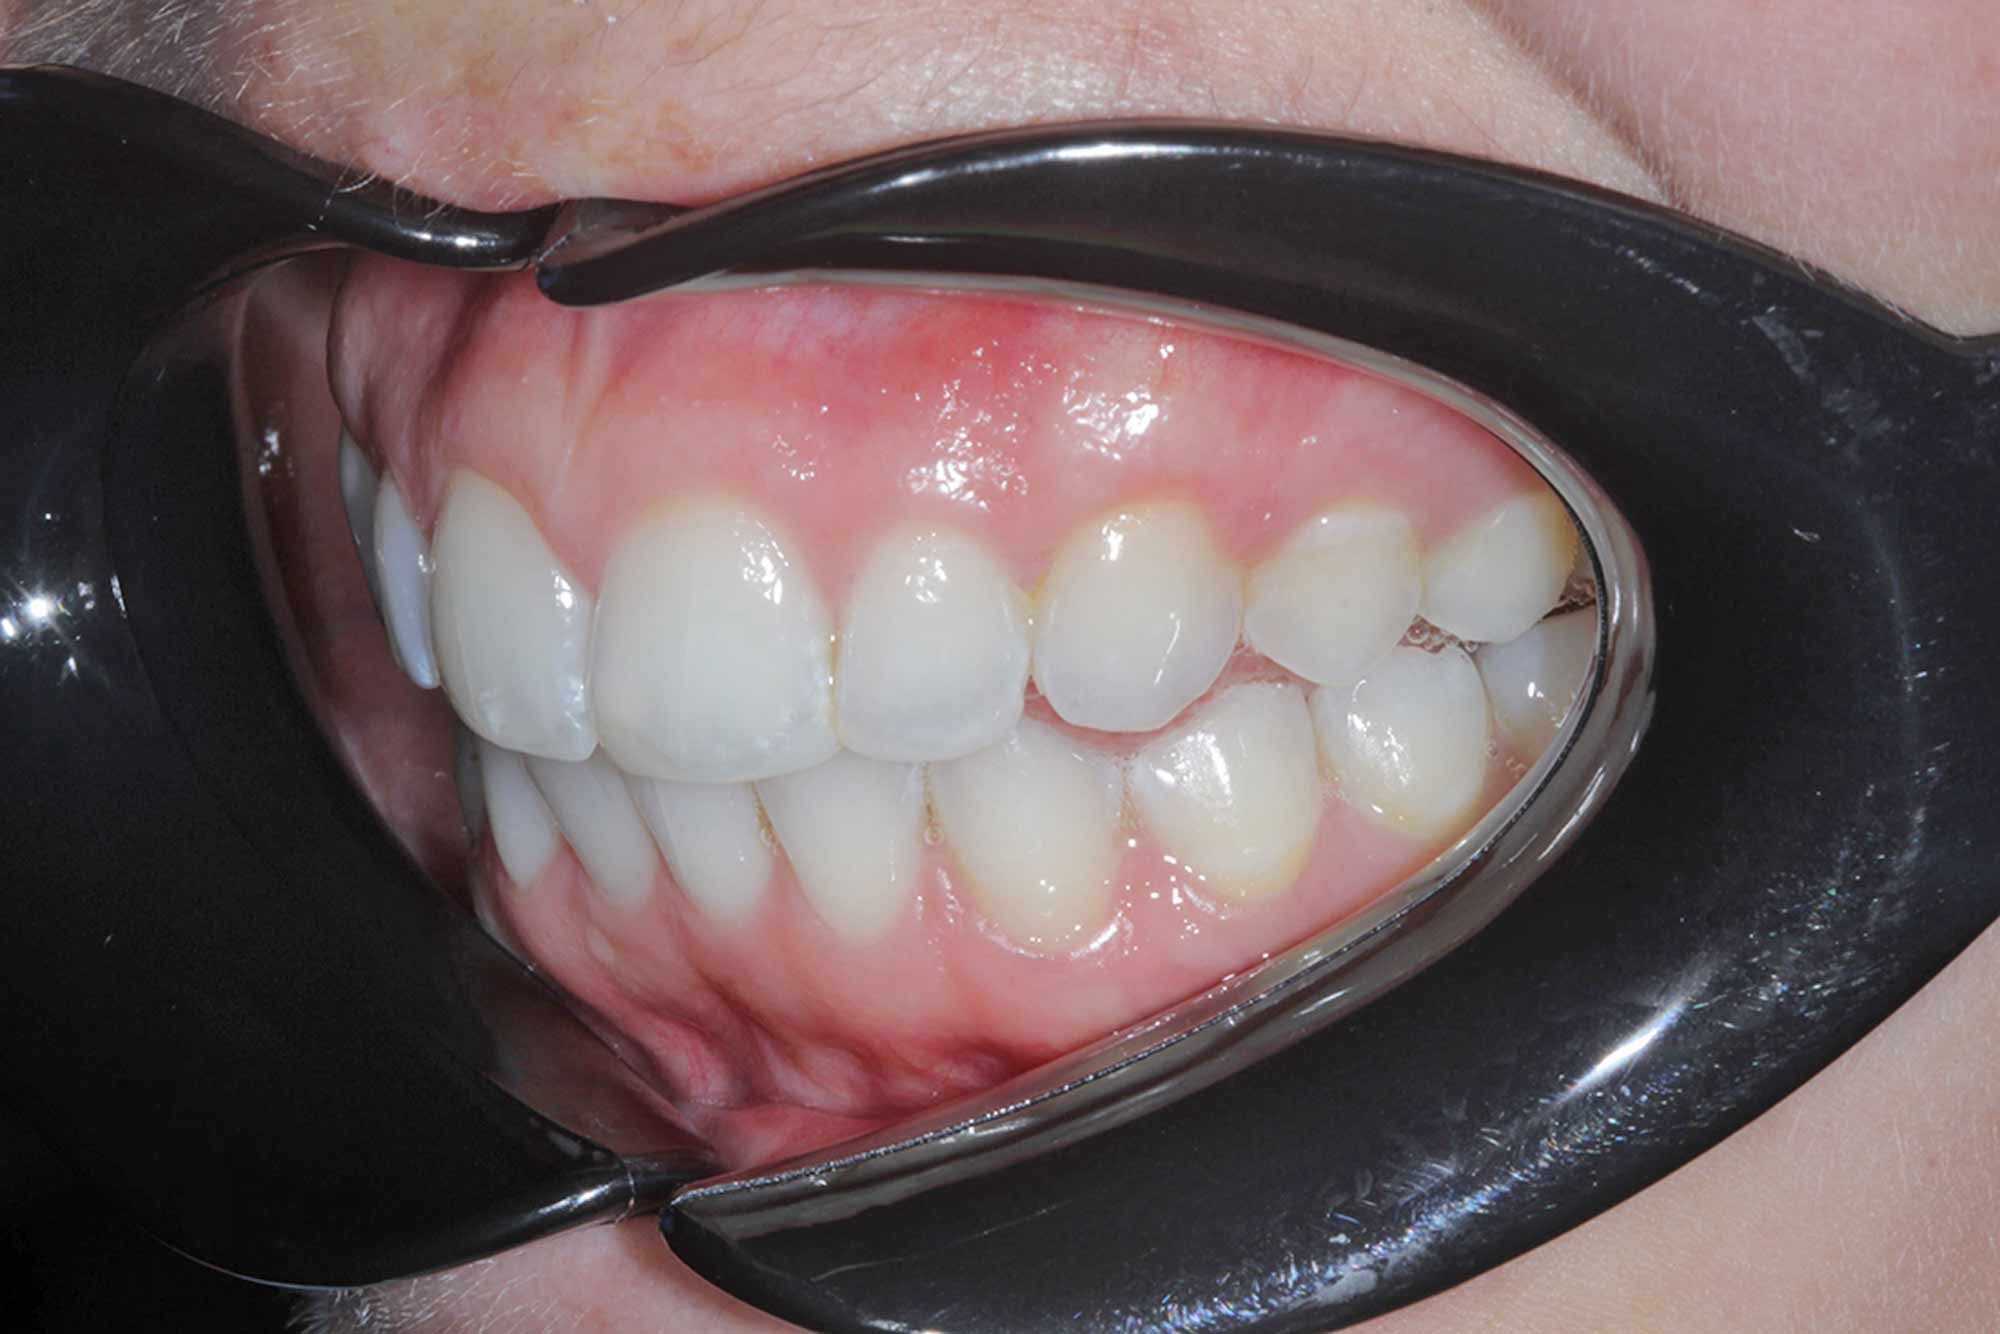

We started off with her aesthetic smile design, as we always do. She had beautiful smile proportions and the potential for perfection was certainly there as we concentrated on matching her gingival margins, widening her buccal corridors and accepting that incisal tooth wear had certainly taken place with some of the edges.

Once we achieved her desired alignment result, the discussion naturally shifted to tooth whitening, and the colour and shade the patient wanted to aim for.

We ultimately achieved a BL1 result, which well exceeded the patient’s expectation.

Once the tooth positioning and colour were both at an exemplary stage, it was time to frame the result with composite direct edge bonding. This has been made much easier due to all the other factors. Our restorative material of choice for this case was Venus Pearl shade BL. This matched the patient’s newly whitened teeth perfectly.

The other factors had been carried out to such a high level, that the bonding stage was very straightforward and fairly easy to conduct. Using the right tools to blend the margins in and polish them to give this case even more longevity in the long run. The key to these cases is anatomy. Match the anatomy and proportions, and it will blend beautifully.

The final result was another delighted patient and another beautiful smile completed following all the smile design protocols. This can incorporate any system needed as long as your planning process is sound and predictable each time.